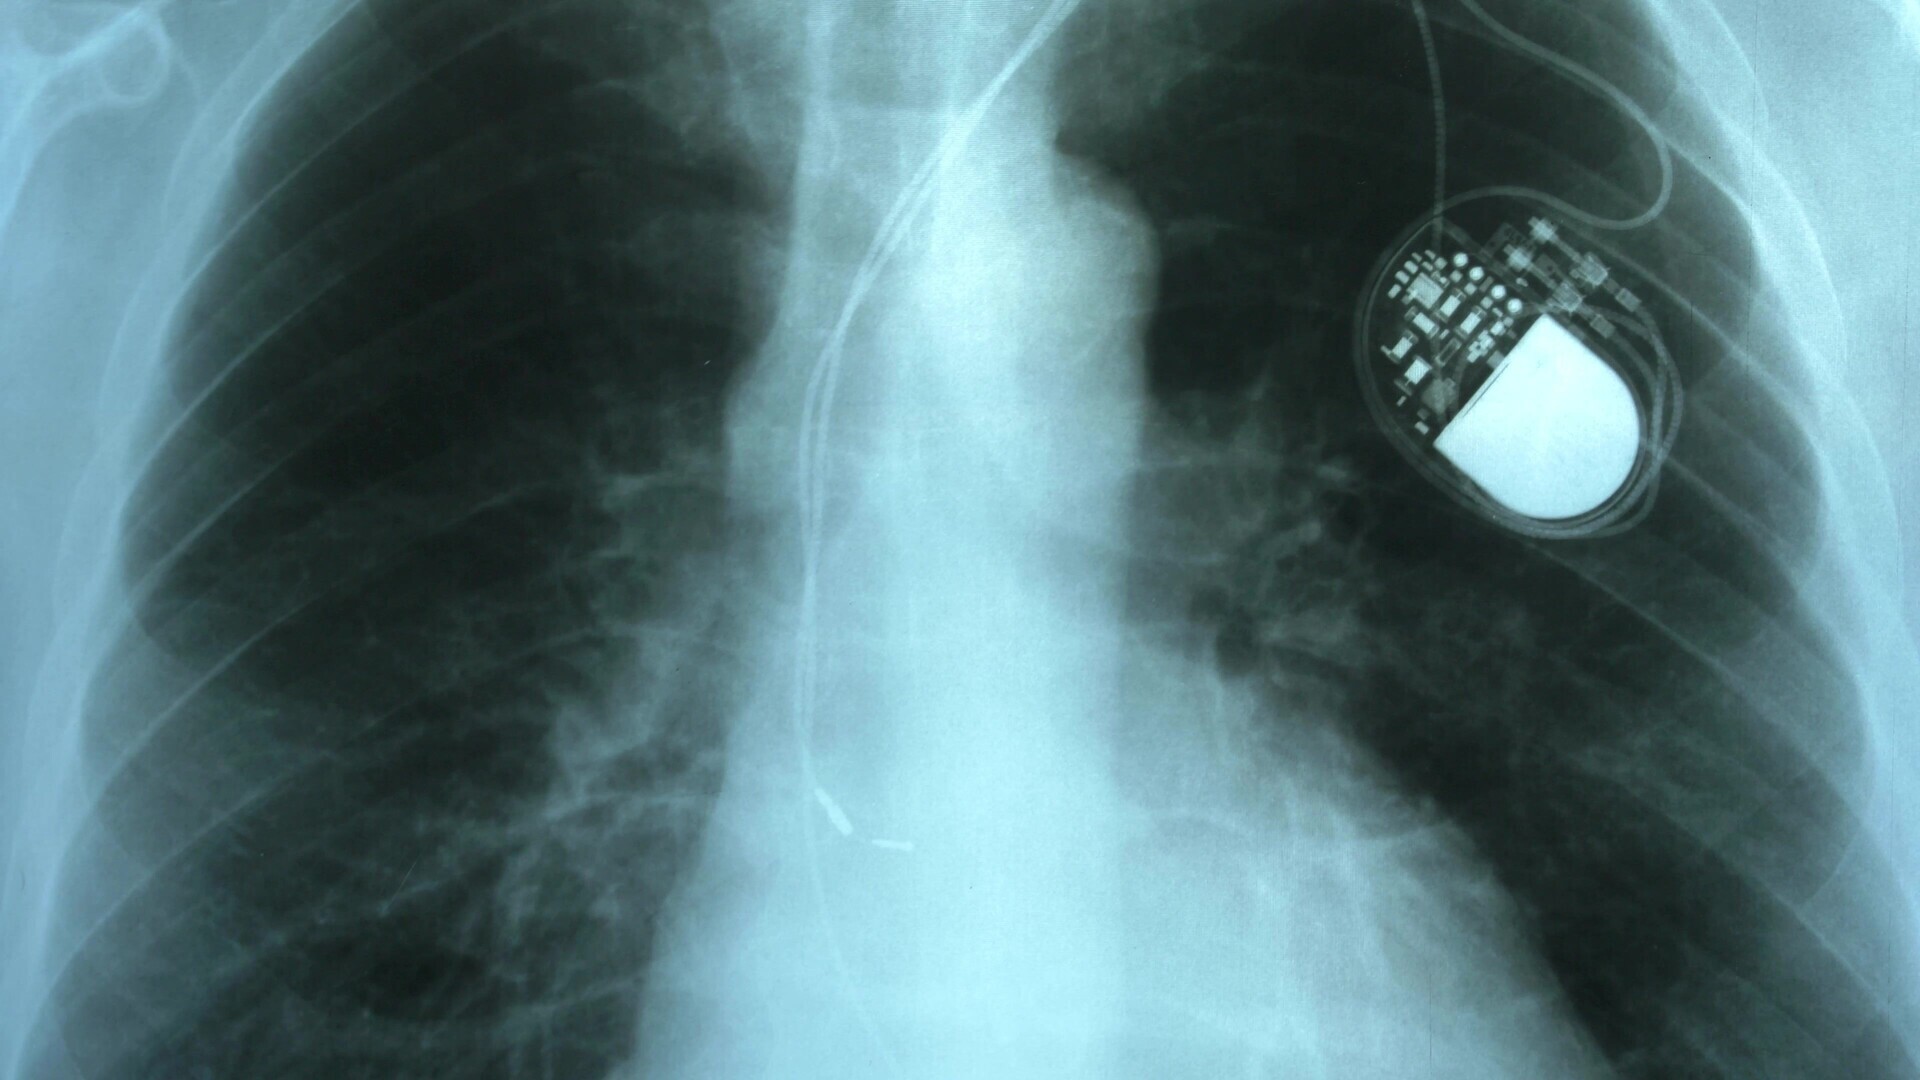

Grundlegende Informationen zur rhythmologischen Krankheitsbildern und ihren Therapien

Auf diesen Seiten finden Sie zu unterschiedlichen Arrhythmien, zu implantierbaren Geräten, zur Telemedizin und zur Schlaganfallprophylaxe grundlegende und wichtige Informationen - von Kolleg:innen für Kolleg:innen.